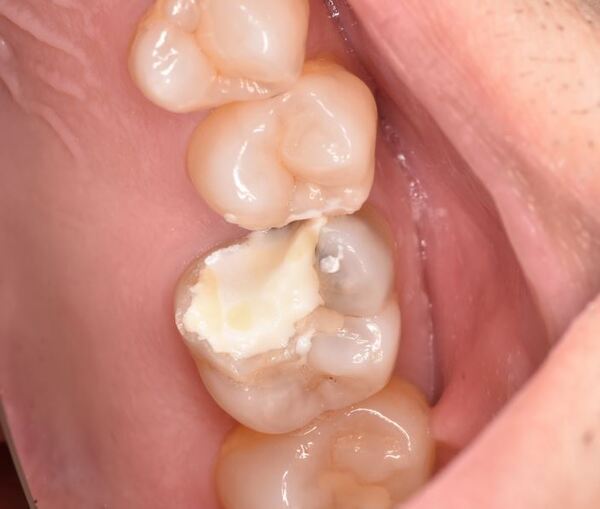

術前のデンタルX線写真と口腔内写真です。右上の前から6番目の歯(#26)です。

術前の診査で、神経が正常に生きていることが分かったので、なるべく神経を温存する治療を進めていくこととしました。

残っている虫歯を慎重に取っている所です。

マイクロスコープを使用することで、虫歯の部分のみを選択的に取り除くことが出来ます。また、神経が露出した際にお口の中の細菌に曝されないようにするために、ラバーダム防湿を行ってやっております。